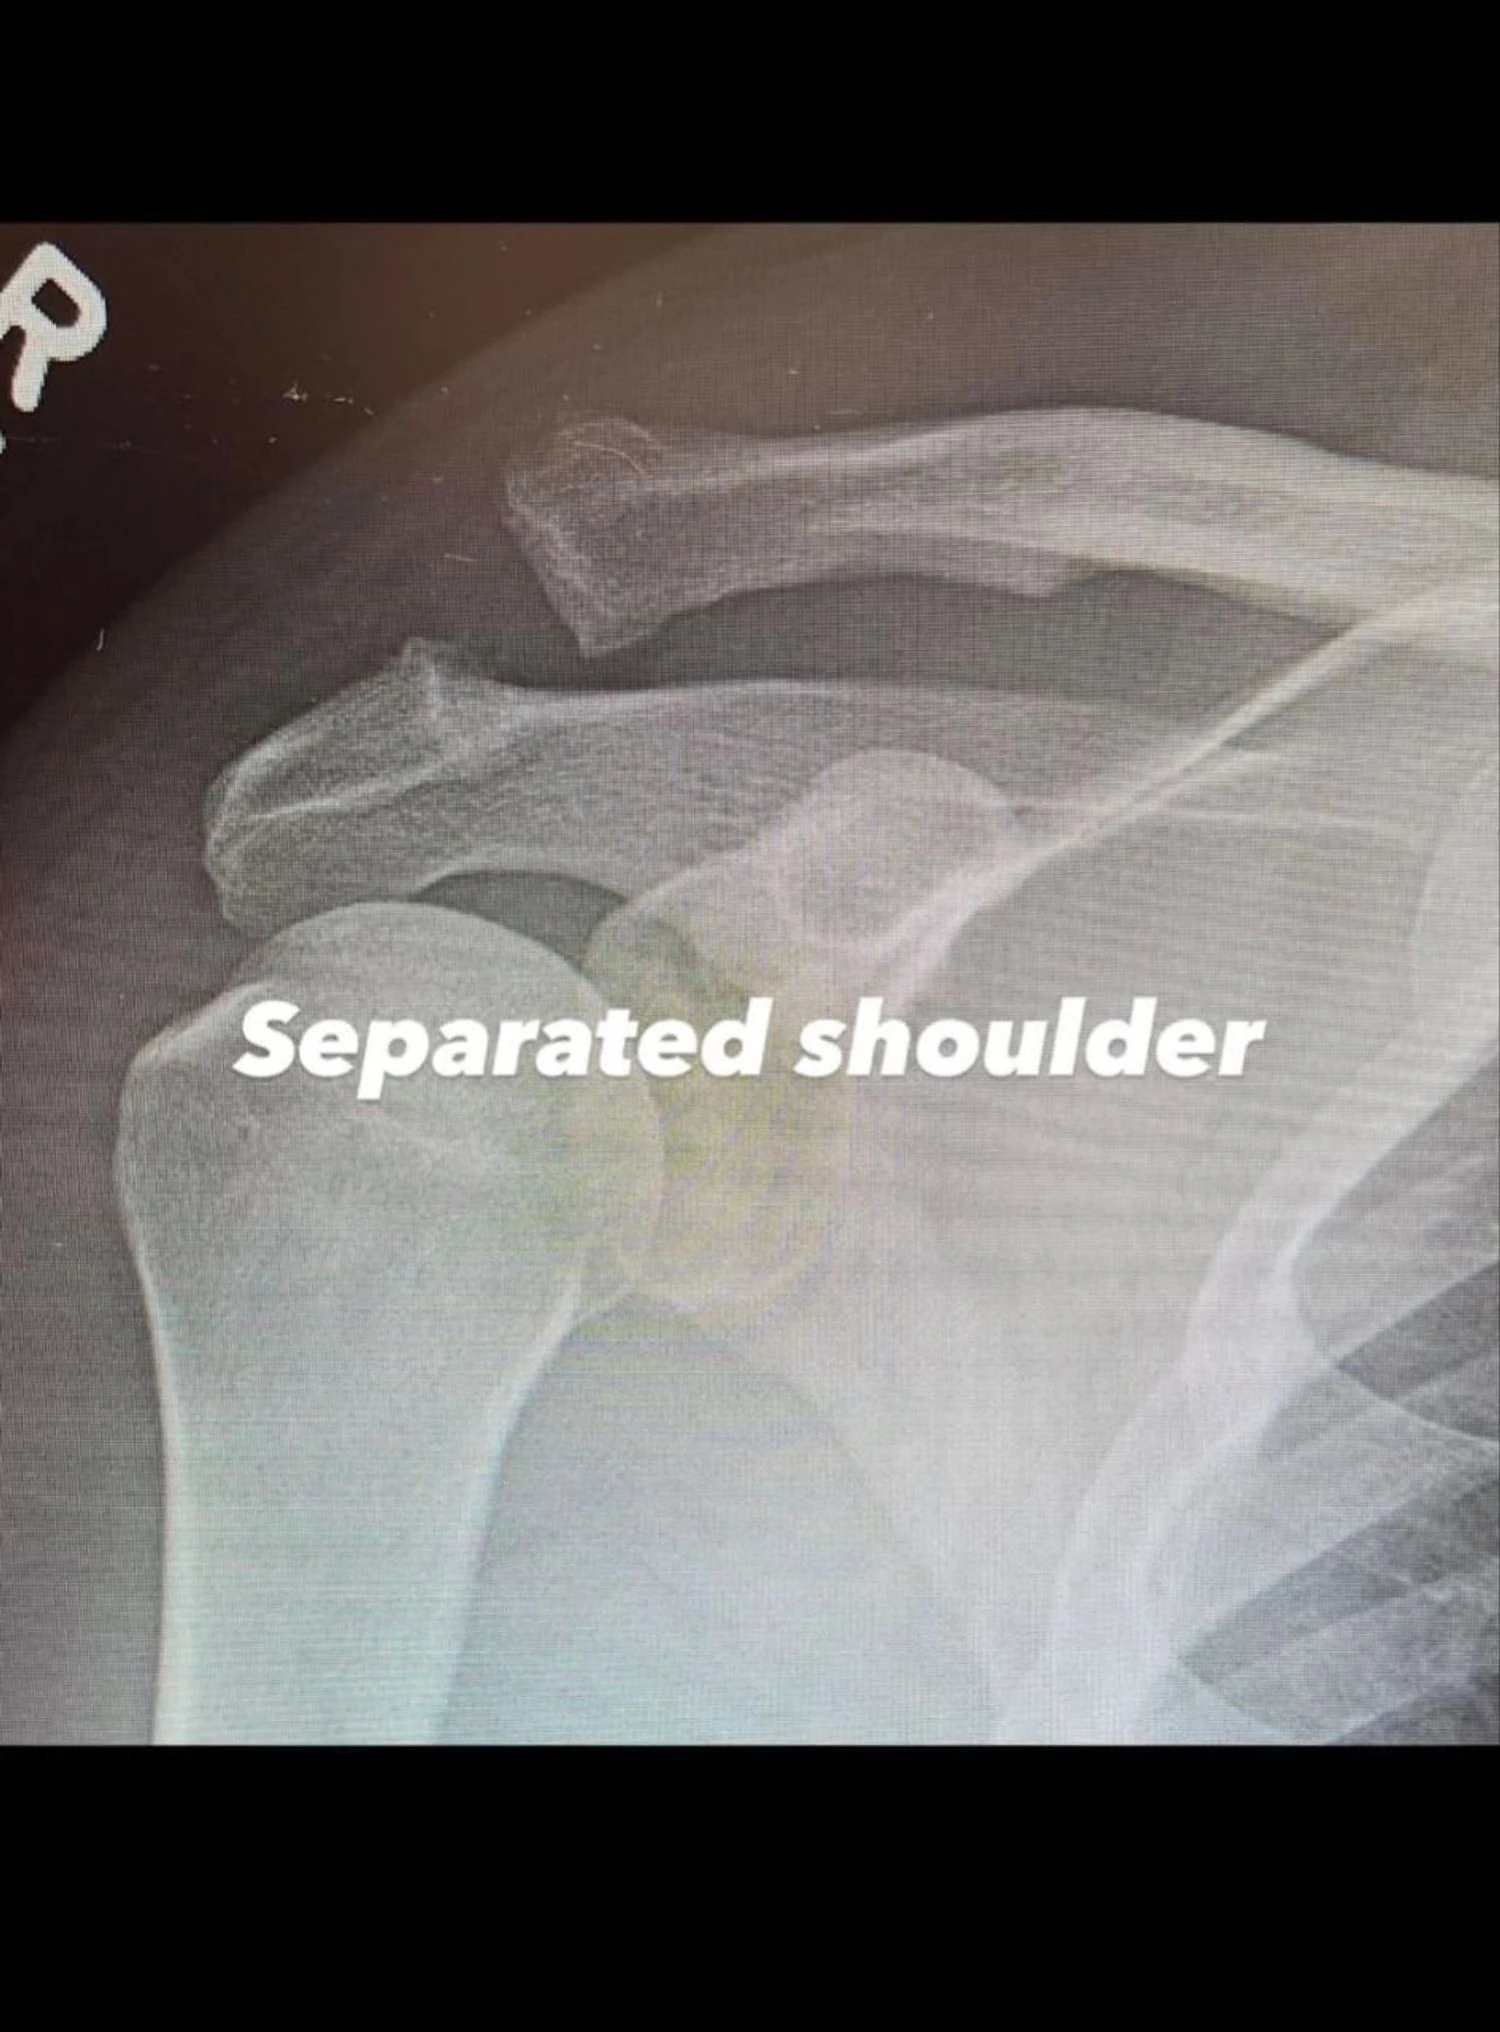

Голливудский актер Ченнинг Татум перенес операцию из-за вывиха акромиально-ключичного сустава. Он опубликовал фото и рентгеновские снимки, заверив фанатов в своем настрое на восстановление.

Как стало известно, операция была необходима из-за вывиха акромиально-ключичного сустава. Чтобы вправить плечо на место, врачам пришлось провести хирургическое вмешательство.

Кроме того, актер поделился рентгеновскими снимками плеча до и после операции. Ченнинг Татум не раскрыл обстоятельства получения травмы, но заверил, что настроен преодолеть трудности и полностью восстановиться.